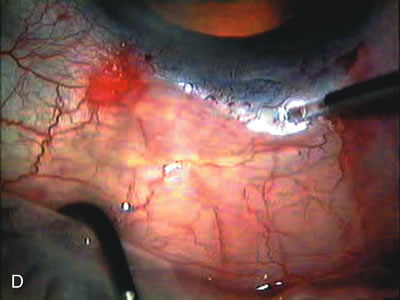

Fig. 4. Viscocanalostomy with deep sclerectomy and phacoemulsification. Nonpenetrating filtration procedures (NPFS) may be combined with phacoemulsification. Patients with mild disc damage and a history of limited topical drug therapy are the best candidates. Patients who require an IOP in the low teens are not good candidates for NPFS. By definition, NPFS is designed to lower IOP without penetrating into the anterior chamber, thereby avoiding the complications associated with trabeculectomy. Viscocanalostomy is intended to allow aqueous to percolate through a trabeculodescemetic membrane into a subscleral cavern created by the deep sclerectomy. The aqueous diffuses from the cavern into the dilated ostia of Schlemm's canal and into the episcleral venous plexus. A. Fashion a uniform 300-micron superficial scleral flap 1 mm into clear cornea. B. Construct a second 600-micron deep flap that facilitates the unroofing of Schlemm's canal, seen as the darker area. C. Use viscoelastic to dilate the ostia of Schlemm's canal. The major problem with viscocanalostomy is the eventual closure of the ostium decreasing flow to the episcleral plexus. D. Dissect the deep flap anteriorly into clear cornea creating the trabeculodescemetic membrane. This membrane is clearly seen between the scleral spur and the bend of the deep flap. The integrity of this membrane ensures the nonpenetrating portion of the surgery. Another problem with NPFS is the eventual fibrosis of this initially transparent membrane requiring goniopuncture. E. Deep sclerectomy gets its name from removal of the deep flap. Removal of this flap creates the potential subscleral space for accumulation of aqueous before it enters Schlemm's canal and exits the episcleral venous plexus. After removal of the deep flap, the superficial flap is sutured into place and conjunctiva closed. Approximately half of these procedures develop a shallow bleb.

Nonpenetrating procedures as they exist today generally decrease postoperative complications but do not reduce IOP as successfully as trabeculectomy.140 The success rate also appears to be highly dependent on race, length of topical antiglaucoma therapy, and prior ocular surgery.141,142 Deep sclerectomy combined with phacoemulsification results in an IOP reduction similar to phacotrabeculectomy at one year with comparable visual outcome.143 Phacoviscocanalostomy lowers IOP by approximately 33%144 through either a one- or two-site approach145 (Fig. 4). Nonpenetrating procedures are in evolution, and their place in long-term glaucoma care is still unclear.